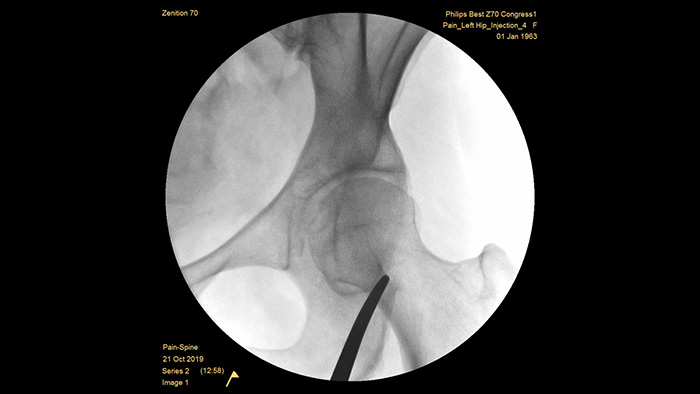

Philips se ha forjado una reputación de excelencia en la obtención de imágenes y la eficiencia de las dosis a lo largo de medio siglo de experiencia en el desarrollo de sistemas de arco en C móviles para el entorno quirúrgico. Nuestras soluciones de cirugía móvil Zenition se basan en un enfoque integral de la gestión de dosis. Proporcionan una calidad de imagen clínicamente relevante durante los procedimientos intervencionistas para aplicaciones de gestión del dolor, al tiempo que gestionan, de forma eficiente, la exposición a la radiación de los pacientes y el personal médico.

Los ajustes únicos del examen de gestión del dolor preconfigurados permiten a los usuarios organizar el sistema con facilidad durante los procedimientos de intervención para el tratamiento del dolor.

MetalSmart excluye automáticamente los artefactos metálicos causados por los implantes metálicos para proporcionar una mayor calidad de imagen y un control eficiente de la dosis para los procedimientos de tratamiento del dolor y para los pacientes con implantes metálicos, en comparación con los sistemas sin exclusión de metales. BodySmart favorece la obtención de imágenes correctas a la primera y la eficiencia de la dosis ya que adapta, de forma automática, el campo de medición a la zona de interés.

La profundidad óptima del arco en C totalmente contrabalanceado proporciona un amplio espacio para posicionarse alrededor de los pacientes obesos, y obtener imágenes de la columna lumbar y la cadera. Admite la colocación sobre la mesa, incluso para las mesas que tienen una base grande.